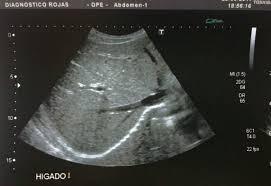

-Ecografía abdominal: riñones de tamaño agrandado (14 cm) y ecoestructura normal. No presenta ectasia pielocalicial.

Hay esplenomegalia de 18 cm, con probables hemangiomas esplénicos y hepático.